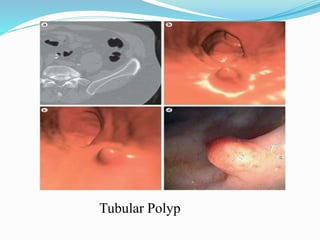

This document discusses colorectal polyps. It defines polyps and describes their types, including neoplastic and non-neoplastic polyps. It discusses adenomatous polyps in depth, noting their malignant potential increases with size over 1cm and villous architecture. Radiological diagnostic methods for polyps including single and double contrast barium enema and CT colonography are explained. The document provides an overview of polyp pathogenesis and genetic syndromes like FAP that increase cancer risk.